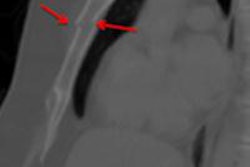

In other news, sagittal reconstructions on chest MDCT studies were found to be useful for identifying sternal injuries.